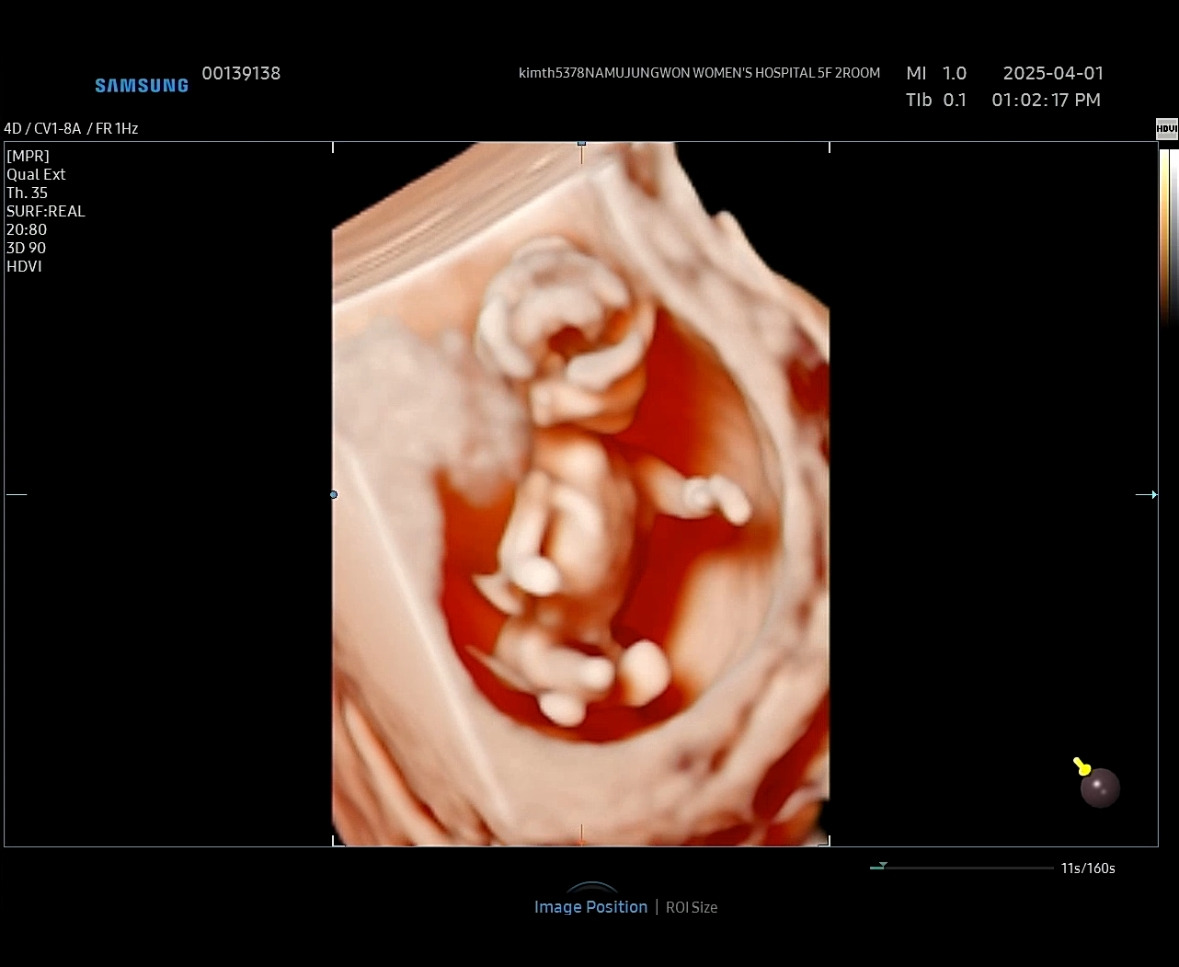

11주 차 6일에 3D 초음파를 봤었는 데, 성별을 알 수 있는 그 부분에 동그란 모양이 보였다. 그래서 나는 아들이라고 초음파 도중에 팡민이에게 크게 말했는 데,

서진을 보면 다리 사이 부근에 동그란 모양ㅎㅎ 근데 3D 초음파는 성별 구분 못한다는 말도 많이 있다. 그냥 초음파가 더 정확하게 보인다고.

팡민이는 저 동그란 걸 보고도 아직 모른다 없어질 것 같다고 했었다. 딸이길 바라는 강한 신념인 걸까..ㅎㅎㅎ